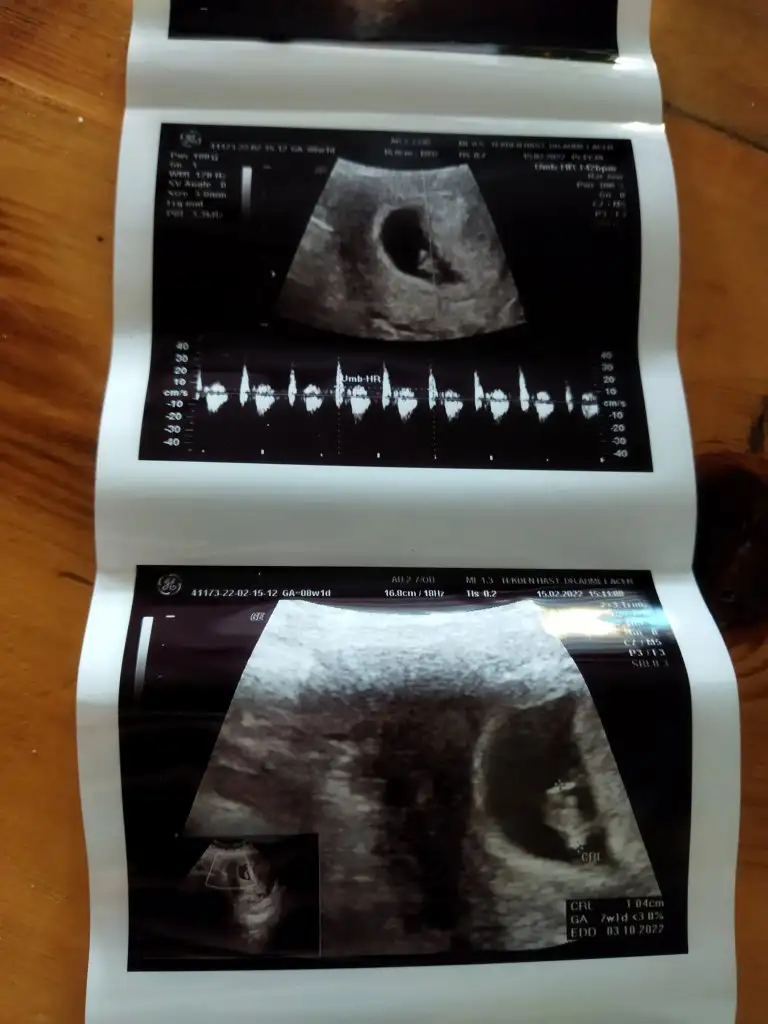

Bana da yorum yapabilir mısınız acaba 7+1 vajinal

Eklentiler